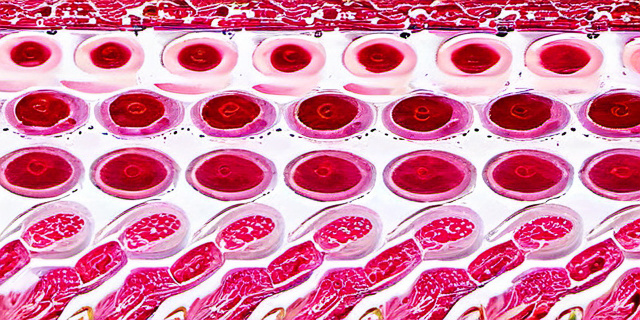

Эстрогены синтезируются в яичниках и надпочечниках, а также в периферических тканях. Основные формы — эстрадиол, эстриол и эстрон. Их метаболизм включает фазы гидроксилирования, конъюгации (с глюкуроновой и сульфатной группой) и дальнейшее выведение из организма.

Кишечник играет критическую роль во вторичном метаболизме эстрогенов, где важную функцию выполняет энтерогепатический круговорот. Эстрогены в конъюгированной форме попадают с желчью в кишечник, где могут быть деградированы или реабсорбированы.

Отдельные бактерии кишечника продуцируют ферменты бета-глюкуронидазы, которые расщепляют конъюгированные эстрогены, высвобождая свободные молекулы, способные к повторному всасыванию. Таким образом микрофлора воздействует на уровень циркулирующих гормонов.